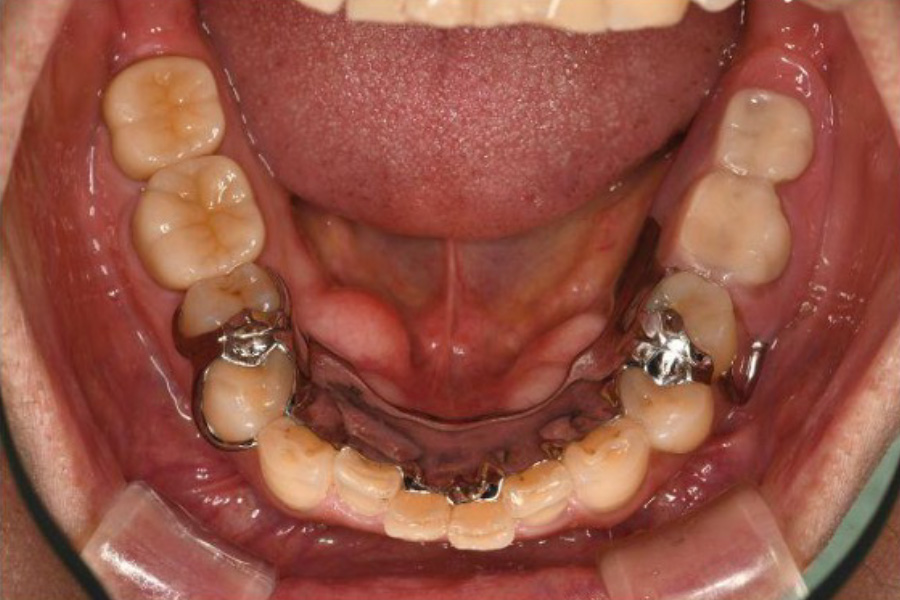

【口腔内写真】下顎咬合面

(噛み合わせの面)の全景

お口の内側(舌側)に見えるボコボコとした突起は「骨隆起」と呼ばれるもので、過酷な噛む力に耐えようとして身体が地盤を厚く補強した、いわば『力のストレス』の顕著な証拠です。

左下奥歯には、破折した根を分割した上で、強固なジルコニアクラウンを装着しています。繰り返された噛み合わせ調整の跡は、いかにこの部位に複雑で強い力が集中していたかを物語っています。

一方の右下奥歯は、激しい摩擦(咬耗)によって歯の表面のエナメル質が消失し、内部の象牙質が広範囲に露出しています。そこにある古い詰め物の周囲には、過度な力による「ヒビ(クラック)」を入り口として、細菌による二次的な虫歯が進行しています。

その他、各所に見られる段差のある不適合な修復物は、細菌の温床となりやすく、お口全体の健康を脅かす構造的なリスクとなっていました。